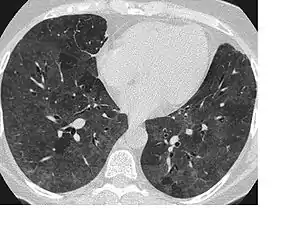

يُشير مصطلح عتامة الزجاج المصنفر - في علم الأشعة - إلى مكتشفات غير مخصصة تظهر بالتصوير الشعاعي والتصوير المقطعي المحوسب، وتأخذ هذه العتامة شكل ضبابي وتحجب الرؤية بشكل جزئي عن التراكيب الشُعبية والأوعية الرئوية أسفلها (تماما مثل الزجاج المصنفر الذي يحجب الرؤية بشكل كامل)، وتدل هذه العتامة على الامتلاء الجزئي للفراغات الهوائية (في الرئتين) بالسوائل، وكذلك قد تدل على السماكة الخلالية أو الانهيار الجزئي للحويصلات الهوائية. [1] :95

يشمل التشخيص التفريقي لعتامة الزجاج المصنفر عدد من الأسباب منها الوذمة الرئوية، العدوى (والتي تتضمن فيروس كورونا المرتبط بالمتلازمة التنفسية الحادة الشديدة النوع 2،[2] الفيروس المضخم للخلايا والالتهاب الرئوي بالمتكيسة الرئوية)، والمرض الرئوي الخلالي غير المعدي (مثل التهاب فرط التحسس الرئوي والالتهاب الرئوي الخلالي الحاد)، النزف الرئوي، التهاب القصيبات المسد لذات الرئة المنظم والرضة الرئوية. [3]